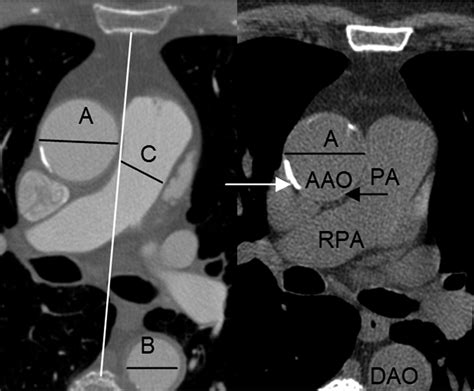

Diagnostic Guidelines for Normal Aorta Diameter

Determining the Normal Aorta Diameter is typically done using non-invasive imaging technologies like Echocardiography, Computed Tomography (CT) scans, or Magnetic Resonance Imaging (MRI). Generally, a measurement in the abdominal aorta that exceeds 3.0 cm is considered the upper limit of normal, whereas anything above 5.0 cm in the thoracic region often triggers clinical concern.

Aortic Root 2.5 – 3.7 cm

Ascending Aorta 2.5 – 3.5 cm

Descending Thoracic Aorta 2.0 – 2.5 cm

Abdominal Aorta 1.5 – 2.0 cm